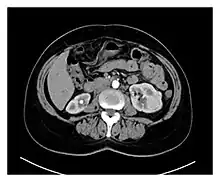

Preoperative contrasted CT scans of the patient, showing multiple bilateral kidney tumors, with diameters ranging between 1 and 5 cm. Radiologically, most of the tumors have malignant characteristics due to their hypervascularity and radiopaque enhancement.